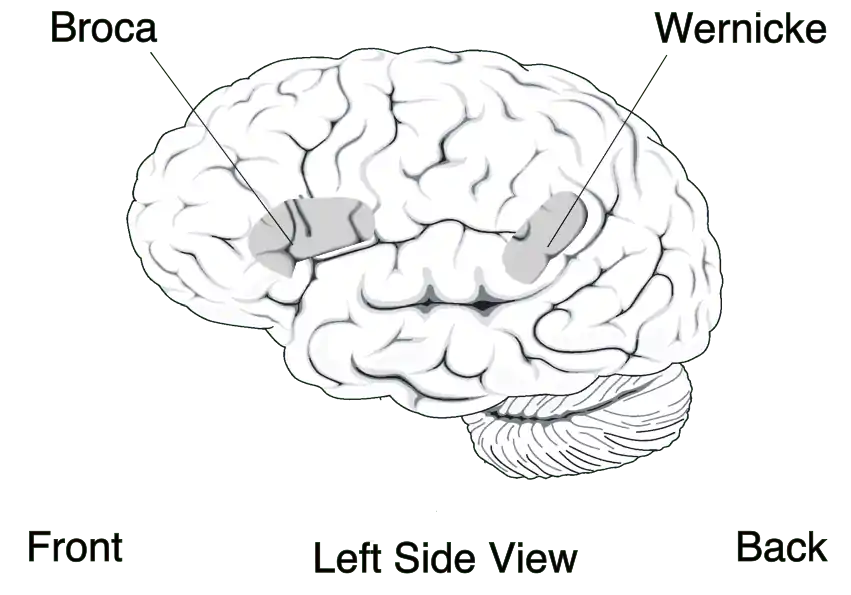

The theory of language localization gained furthur credit with significant findings attributed to Paul Broca in the 1860s. [2] The beginning of comprehensive Aphasia understanding came with Paul Broca’s research and subsequent description of his patient Laborgne's brain. In 1861, Broca published “Remarques sur le siège de la faculté du langage articulé: suivies d' une observation d'aphémie” in which he evidences for the localization of articulate speech in the frontal lobe. [1] Upon Leborgne’s death, Broca performed an autopsy and determined that the damage was suffered to the third convolution of the left frontal lobe, which is now commonly referred to as Broca’s area. [2] Stemming from his influential findings, was a revolution in medical and physioogical thinking as it pertained to the brain and the establishment of cerebral localization. Less than a decade later, Wernicke identified “sensory” aphasia as being localized to the temporal lobe. [1] Ludwig Lichtheim then branched off of Wernicke’s model, naming five other types of aphasia, pure word deafness, conduction aphasia, apraxia of speech, transcortical motor aphasia, and transcortical sensory aphasia.